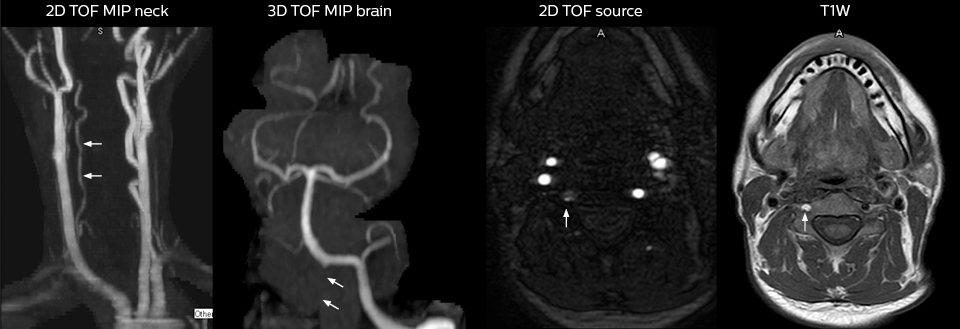

“We use mDIXON TSE extensively in our spine imaging in the emergency room,” says Dr. Karis. “It’s particularly nice in that it is very robust with regard to susceptibility type of problems that would come up with traditional spectral fat-saturated images; these problems are essentially eliminated with the mDIXON technique. In our ED environment it’s really nice to have the fat-free imaging that goes along with the mDIXON technique.

“For the thoracic and cervical spine routine non-contrast exam, for example, we perform one mDIXON T2 TSE sequence, which provides us with two outputs: the fat-and-water-together T2-weighted images, as well as the water-only sagittal T2-weighted images. And then we also perform an axial gradient echo exam.”